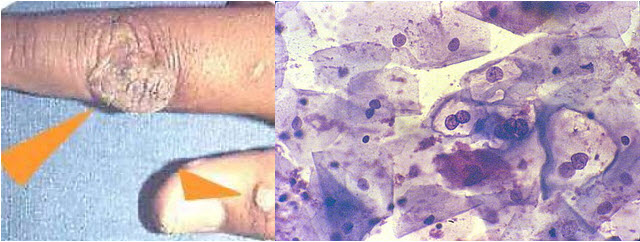

Možete li sami pokušati da odgonetnete šta bi mogao da bude uzrok poremećaja kod ovog čoveka iz Indonezije?